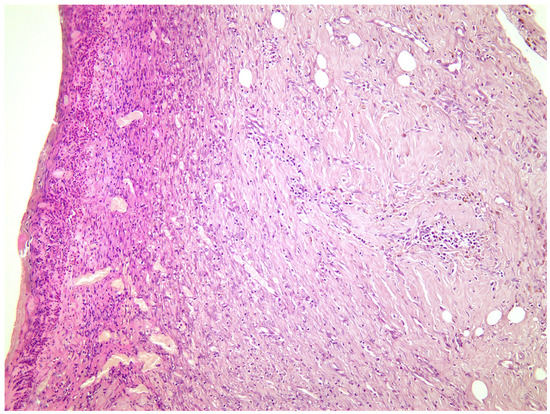

2.2. Histological Study

—fibrin clot,

—granulation tissue,

—fibrotic tissue,

—adipose tissue.